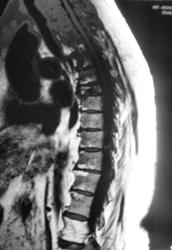

Пациентка - мама нашего коллеги. Жалобы на боли в позвоночнике.

На мой взгляд в верхнегрудном отделе наиболее выраженные изменения опухолевой природы, хотя и на других уровнях есть изменения. По отдельным слайдам не складывается полная картинка, аксиальных томограмм этого отдела нет совсем.

Не опровергая мнения Евгения Второго: а не выглядит ли то, что "не красиво" в верхнегрудном отдлеле как "артефакты"? Складывается впечатление, что "изменения" с тел позвонков переходит на средостение и на грудину... Картинка как бы в "градиенте"... По остальному позвоночнику - дегенеративные изменения + гемангиомы + последствия компрессионного перелома тела позвонка; возможно ошибаюсь... Нужно смотреть шейно-верхнегрудной...

Спондилит туберкулезный..

спондилит то есть, с компрессией тела позвонка и паравертебральными изменениями. и если вверху артефакты (граница каналов катушки, неправильное позиционирование или типа того) - тогда спондилит выходит на первый план. только насчёт туберкулёзного я бы не стал так уж уверенно. может просто опыта нет в дифдиагностике туберкулёзного и банального спондилитов (у меня).

Компрессионный перелом позвонка, вокруг изменения мягких тканей, похожие на натечник. Хотя рассмотреть бы это в нормальном качестве... DICOMа нету?

Я не занимаюсь сам, этими прекрасными высокими технологиями. После исследования, проведенного в области были выставлены множественные гемангиомы. Боли в позвоночнике у пациентки были и ранее, но в определенный момент резко усилились, по всей видимости, тогда и произошла "компрессия". Мне не верится, что это гемангиомы. Я более склонялся к специфике (туб спондилиту), но это мнение во многом больше интуитивно.